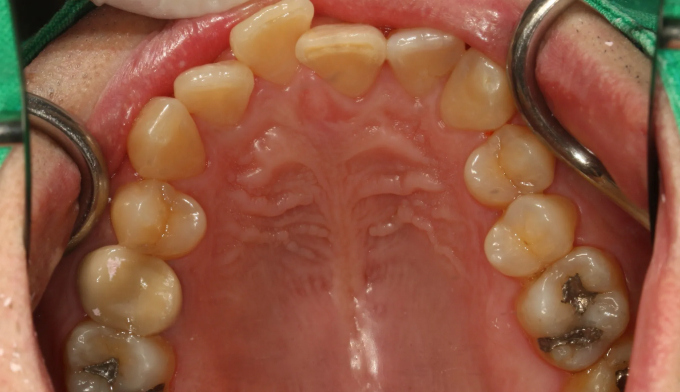

앞니에 치아를 배열할 공간이 부족해 보입니다. 또한 과도한 교합력으로 인해 아래 앞니가 거의 안보이는 과개교합이 관찰되며, 해당 부위의 뼈도 웃자라 있는 골융기가 관찰됩니다.